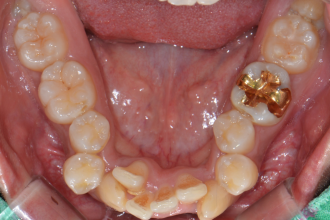

치아교정